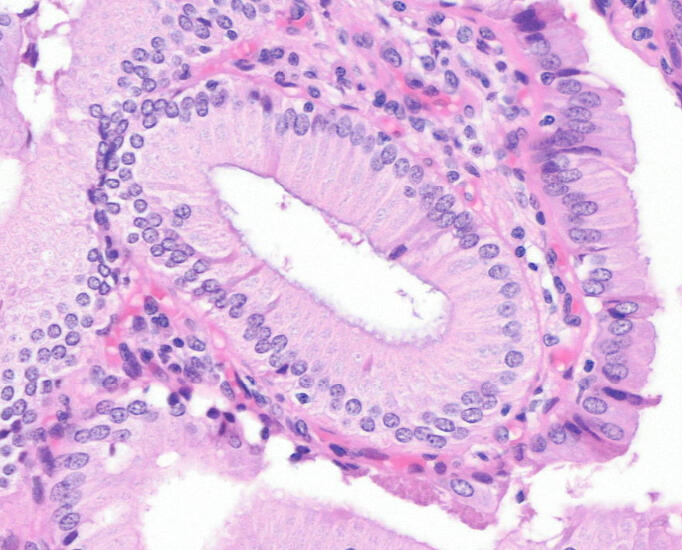

Our models generate IHC–equivalent images directly from standard H&E slides - no reagents, no waiting. Using generative AI trained on thousands of paired samples, we reproduce biomarker expression patterns at cellular resolution.

Our generative models create realistic, privacy-preserving histopathology images to augment datasets and accelerate AI development, leading to more robust and generalizable models.